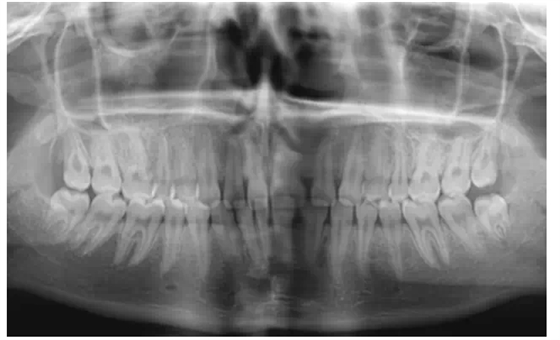

2、拍攝x線片

在修復(fù)前要判斷患者的牙周情況和牙齒的治療情況,做到知己知彼,為成功修復(fù)打下良好基礎(chǔ)。

曾有一個(gè)這樣深刻的教訓(xùn),患者因?yàn)榍把烙锌p,想做貼面修復(fù),剛做完的效果是很好的,可是過(guò)了半年,牙齒又出現(xiàn)了縫隙,通過(guò)x線片的檢查發(fā)現(xiàn),牙槽骨的吸收比較嚴(yán)重。所以,一定要對(duì)患者的牙周情況進(jìn)行充分的把握。